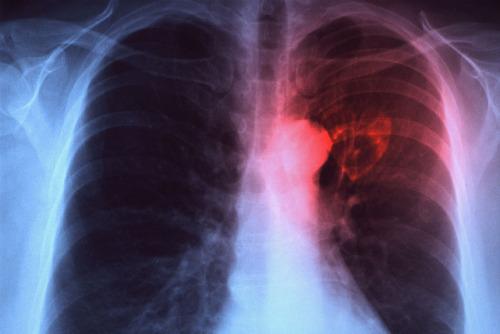

Infectiile respiratorii sunt prima cauza de imbolnavire a copiilor, Foto: Captura YouTube

La nivel global, pneumonia este principala cauza de mortalitate infantila, informeaza Organizatia Mondiala a Sanatatii. Pneumonia ucide mai multi copii cu varsta sub 5 ani decat orice alta boala. Mortalitatea infantila este corelata cu aspecte precum: alimentatia deficitara, saracia si lipsa de ingrijire medicala (acces la servicii medicale, informatii corecte, etc.) Cum ar putea fi prevenita pneumonia?